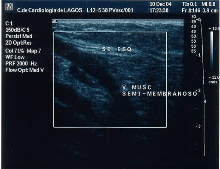

The small saphenous vein (SSV), runs along the posterior aspect of the leg as far as the popliteal region, in the upper calf. Here it enters the popliteal space which is located between the two heads of the gastrocnemius muscle where it usually drains above the knee joint in the popliteal vein or a little less often in the great saphenous vein (GSV) or other deep muscular veins of the thigh.[52] The use of ultrasonography has allowed a number of variations to be shown at this level; when no contact is made with the popliteal vein it might be seen to drain in the GSV, at a variable level; or, it may merge with the Giacomini vein and drain in the GSV at the superior 1/3 of the thigh. It can also but rarely, drain in the vein of the semimembranosus (thigh muscle) (shown below). Usually though, it connects with a perforator vein at its middle 1/3.[22] To check for insufficiency, the Paraná maneuver is very useful.[35]

![]() SSV variant draining in the vein of the semimembranosus muscle |